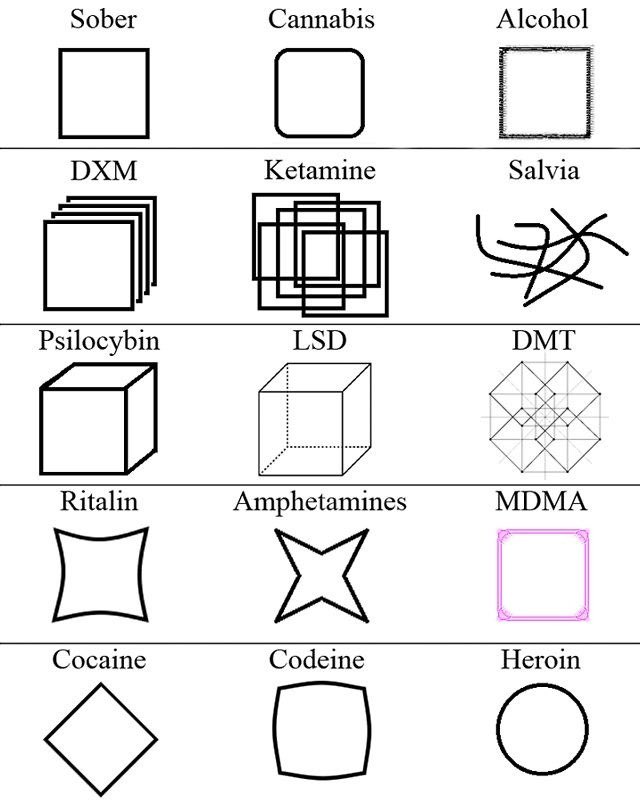

首先,从定义上讲,“反解离(anti-dissociative)”并不是一个标准的医学术语或者广泛认同的药理学分类。在正规资料,比如医学文献、维基百科、精神药理学教科书中,目前并没有“反解离药物”这个正式概念。

看上去像是为了描述某类特定效应而创造的术语(可能是nmda受体活性增强),用来对抗因NMDA受体拮抗剂(比如氯胺酮、DXM、PCP等)引发的解离体验(dissociation)。

那么更常见的是将其归入认知增强剂(cognitive enhancers),特别是改善认知连接性(connectivity)和现实感知(reality testing)的类型。

但其实在药理学上,单纯用“受体激动剂”来逆转“受体拮抗剂”的效应,有时会导致过度激活。

对于NMDA受体而言,过强的NMDA活化本身就与兴奋性毒性(excitotoxicity)和精神病样症状(psychotomimetic effects)有关,比如谷氨酸风暴可以引发严重的焦虑、妄想、乃至癫痫。

也就是说,简单地“激动-解除拮抗”在中枢神经系统是很危险的做法,尤其是对于易感个体(如有精神分裂素质的人)。

科学的处理方式一般是通过更细致的调节,比如微调NMDA/AMPA平衡、调节其他辅助途径(如GABA、5-HT、mGluR受体),而不是简单粗暴地用“NMDA增强剂”去顶回去。

而临床处理药物中毒中,其实医生更常用的做法是保守、支持性的治疗,比如补液,促进代谢,必要时镇静,以及监测生命体征防治并发症。

金刚烷胺会对神经系统造成长期/不可逆的影响

金刚烷胺作为多巴胺释放促进剂,在长期使用或过量下可能导致:

-DA系统适应性衰竭(Receptor downregulation)

-药源性多巴胺枯竭综合征:表现为认知退化、动机缺失(apathy)、情绪迟钝等。

NMDA

虽然金刚烷胺是弱NMDA拮抗剂,但长期使用可能导致:

-突触可塑性损伤(LTP/LTD受阻)

-情景记忆下降、学习能力减退

-焦虑、攻击行为升高

-神经元代谢负荷增加,增加兴奋毒性风险

金刚烷胺提高兴奋性毒性(NMDA活性失衡、多巴胺代谢紊乱),与致幻剂合用或交替用药会:

-加剧皮层-边缘系统的不稳定性(例如海马体、前额叶)

-增加精神病风险(psychosis risk)

-导致长期认知损伤与感知畸变的残留症状(HPPD-like states)

另外有导致神经适应性结构改变

动物研究提示,金刚烷胺长期使用可能导致:

-树突棘数量下降

-突触可塑性衰退

-神经炎症因子(如IL-6)升高,为不可逆脑损伤打下基础

2025-04-29 11:45:39 UTC

简版

金刚烷胺不但无法提供真正的致幻体验,反而会破坏大脑、干扰神经系统,带来无法逆转的损害。

短期风险:

-幻觉质量差、碎片化,常伴恐惧、迷惑、妄想

-谵妄状态(严重的意识混乱)

-焦虑、失眠、暴躁、攻击性升高

-心跳紊乱、口干、头晕、甚至癫痫发作

长期风险:

-损伤大脑中的多巴胺与谷氨酸系统

-学习能力下降、情绪变平淡、认知迟钝

-增加患上药源性精神障碍的风险